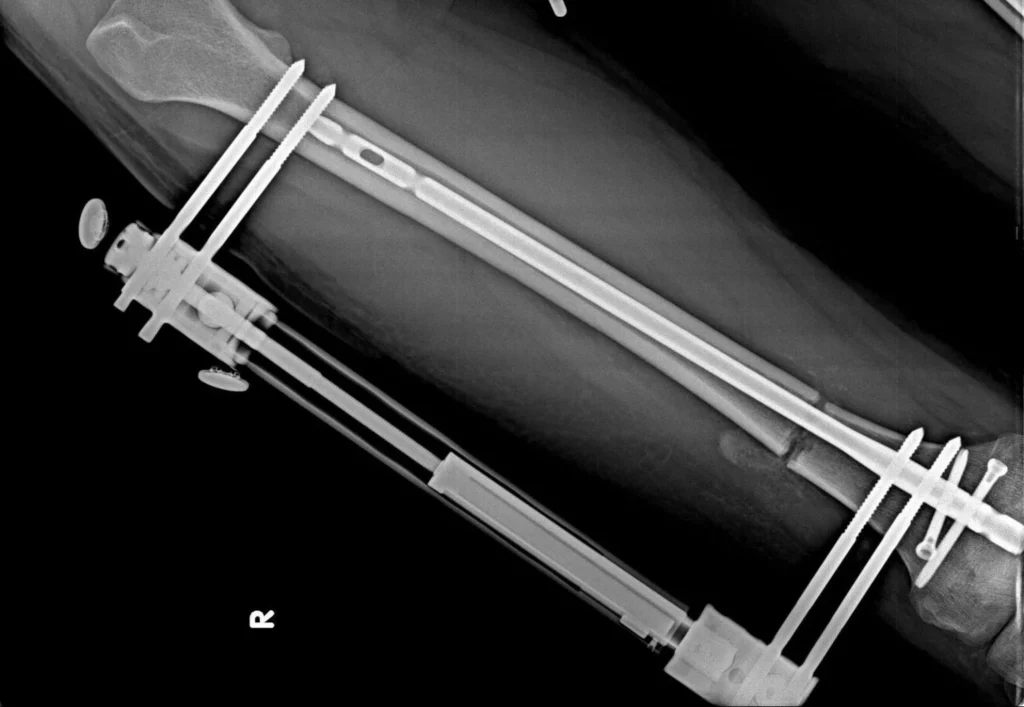

An external fixator is a robust support system used in limb lengthening procedures to stabilize the bone from the outside. It plays a critical role in ensuring proper bone healing by keeping the bone steady throughout the lengthening phase. The device, made of strong metal rods, is securely attached to the bone with specialized pins, allowing the lengthening process to proceed in a safe and controlled manner.

It is applied during surgery and typically remains on the leg for about 2 to 3 months, depending on the planned lengthening. During this period, the external fixator maintains bone alignment, preserves stability, and supports healthy bone regeneration as the lengthening continues.

These are titanium intramedullary nails specifically designed to be compatible with the human body and are used to support the bone during limb lengthening procedures. They help maintain stability and ensure that the lengthening process progresses safely. The appropriate nail size is determined by the surgeon after evaluating the patient’s X-ray images and is typically selected from options such as 8.5 mm, 10.7 mm, 11.5 mm, or 12.5 mm.

During the operation, the nail is inserted into the inner canal of the bone. Thanks to its biocompatible properties, it does not cause harm to surrounding tissues and does not trigger adverse reactions within the body.

To ensure proper alignment and stability, an intramedullary nail and an external fixator are applied. Around the fifth day after surgery, the lengthening phase begins. Patients gradually lengthen the bone by approximately 1 mm per day by adjusting the device. This is typically done by turning the screws every 6 hours, achieving 0.25 mm with each adjustment.